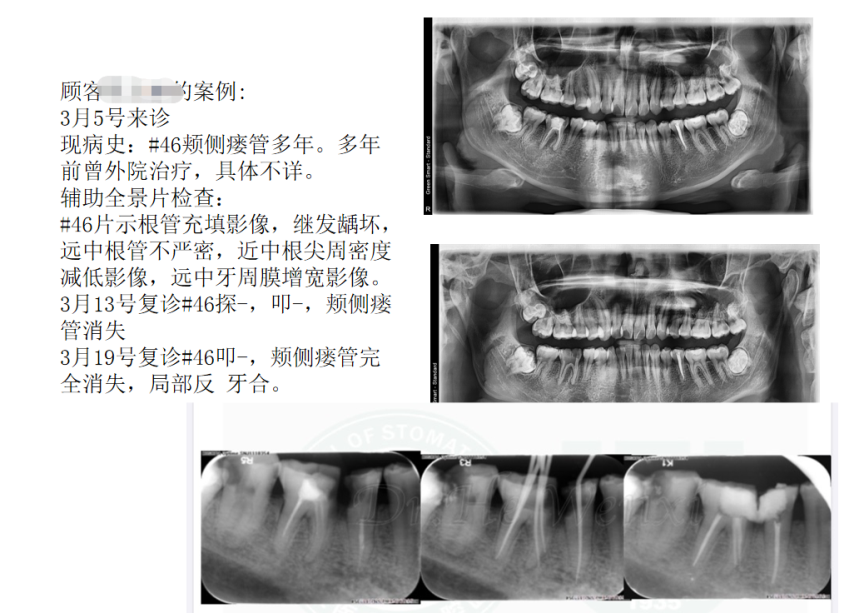

一、瘺管案例的處理和治療

王娟醫生以近期一個顧客的治療作為案例,就整個顧客的到診情況、治療過程、治療結果展開詳細分享,完整闡述了針對瘺管情況的有效治療方式和與醫患溝通協調。